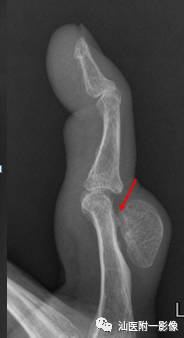

4.甲下外生性骨疣 (新增)

•一种累及远节指(趾)骨末端的骨软骨瘤样增生。

•最常累及踇趾,很少累及其他指(趾)骨。

•发病高峰10~30岁,男性多见。

引自:Redouane O, El Bardouni A. [Nail nodule in athletes: think of subungual exostosis]. Pan Afr Med J. 2015 Apr 23;20:402.